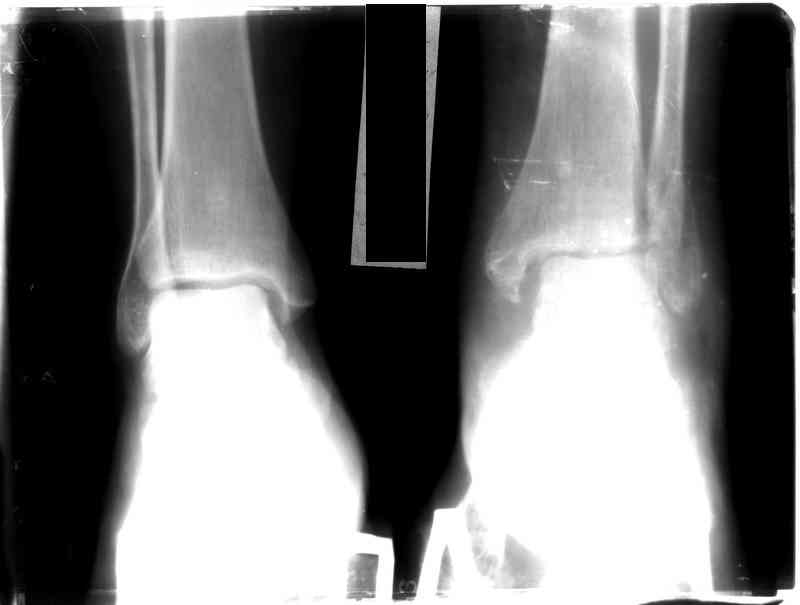

Перелом обеих лодыжек и з/края б/б кости с вывихом стопы,new |

Ув. коллеги, я уже сообщал об этом случае недавно. Металлоконструкции удалены через 7 недель с момента травмы, после чего еще месяц иммобилизации, осторожная дозированная нагрузка. Спустя 3,5 месяцев имеем следующее. Что порекомендуете? С ув. Sergey A. Melashenko ул. Кирова 88-А, г. Приморск, Запорожская обл., 72100, Украина

Ув. Максим. Движения в суставе в полном объеме, беспокоят выраженные боли в суставе, сохраняется отек. Осевая наргрузка болезненна, особенно

в проекции синдесмоза. Похоже вся проблема в синдесмозе. Может обождать, пока окрепнет наружная лодыжка и провести операцию, как при застарелом

повреждении синдесмоза (болт-стяжка или что-нибудь поновее)

Склоняюсь к мнению, что тактика лечения такой больной была не совсем адекватна, необходимо было в первые 2-3 суток (после проведенной репозиции) произвести остеосинтез по АО с позиционным винтом или даже

ургентно, в первые часы после травмы.